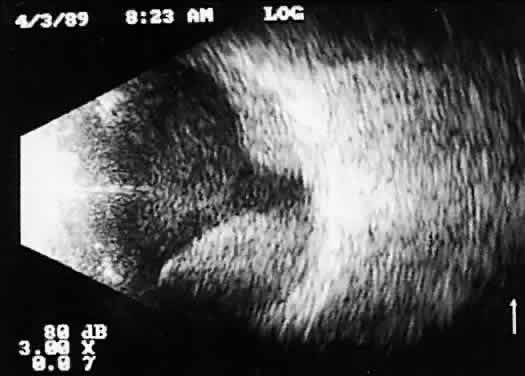

TRAUMA AND FOREIGN BODY EVALUATIONS

Ultrasound examinations for ocular trauma and intraocular foreign bodies are among the most difficult, for a variety of reasons (Figs. 14 and 15). The examiner is often presented with recently injured, unstable, or open globes with multiple complex injuries. Extreme care is necessary to avoid undue pressure during ultrasound evaluation, and concerns for contamination are significant. Understandably, probe contact is often minimized, and unless additional sterile methylcellulose solution is used to improve signal transfer, less-than-optimal images result. These poor-quality images are difficult or impossible to interpret, especially in opaque media situations with multiple abnormalities. Further, patient noncompliance and the examiner's inexperience frequently lead to incomplete examination, limiting 3D analysis.

Fig. 14. Contact B-scan: choroidal hemorrhage/vitreous hemorrhage secondary to blunt trauma.